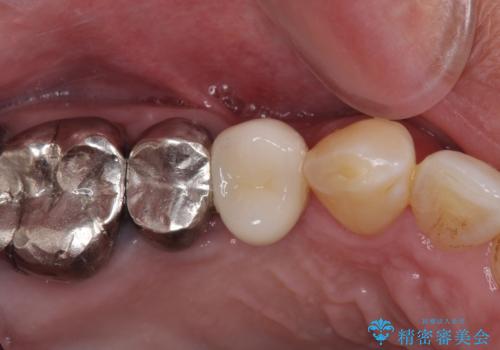

折れてしまった奥歯 インプラントによる補綴治療

- 奥歯に違和感を感じており、抜歯の必要性を感じて来院された患者様です。

診査の結果、5本の奥歯を抜歯してインプラントによる補綴治療が必要と診断されました。

患者様が違和感を感じていない左下の奥歯の治療は今回は見送り、それ以外の治療が必要な奥歯を治療することとしました。